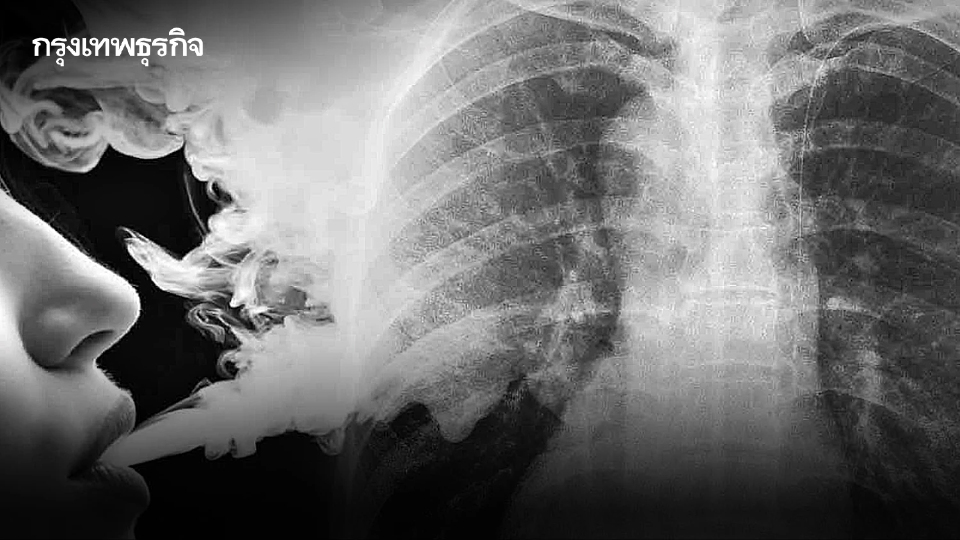

สำหรับ “บุหรี่ซอมบี้” มีส่วนผสมของสารเอโทมีเดท (Etomidate) ยานำสลบที่ใช้ในทางการแพทย์ หากใช้ในทางที่ผิดเหมือนยาเสพติด ทำให้ง่วงซึมอย่างรุนแรง อัตราการหายใจลดลง หรือเกิดภาวะหายใจช้าลงจนเป็นอันตราย ความดันโลหิตต่ำ คลื่นไส้อาเจียนสับสน หมดสติ อาจทำให้เสียชีวิตได้ ขออย่าหลงเชื่อคำชักชวนว่าปลอดภัยหรือลองแค่ครั้งเดียวไม่เป็นไร ทั้งนี้ นอกจากพบแพร่ระบาดในสถานบันเทิงแล้ว ยังพบการลักลอบจำหน่ายผ่านช่องทางออนไลน์และในสถานที่รวมกลุ่มต่างๆ โดยมักอ้างสรรพคุณว่าทำให้ผ่อนคลายและนอนหลับสบาย

บุหรี่ซอมบี้ คือบุหรี่ไฟฟ้าที่มีการผสมสาร Etomidate ลงไปเพื่อให้ออกฤทธิ์เหมือนยาเสพติด บุหรี่ไฟฟ้ามีผลกระทบกับสุขภาพผู้สูบมากมาย ยิ่งมีการผสมยาและสารต่างๆ ลงไปยิ่งอันตรายเพิ่มมากขึ้น ถึงแม้จะมีการเลิกสูบไปแล้วแต่ยังส่งผลในระยะยาวต่อฮอร์โมนที่ต่อมหมวกไต ทำให้ร่างกายไม่สามารถสร้าง ฮอร์โมนคอร์ติซอล (Cortisol) ส่งผลให้การทำงานของกล้ามเนื้อผิดปกติ